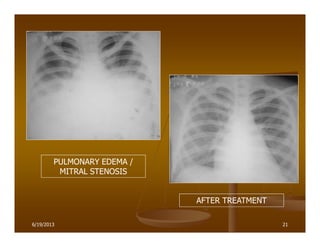

PULMONARY EDEMA /

MITRAL STENOSIS

AFTER TREATMENT

6/19/2013